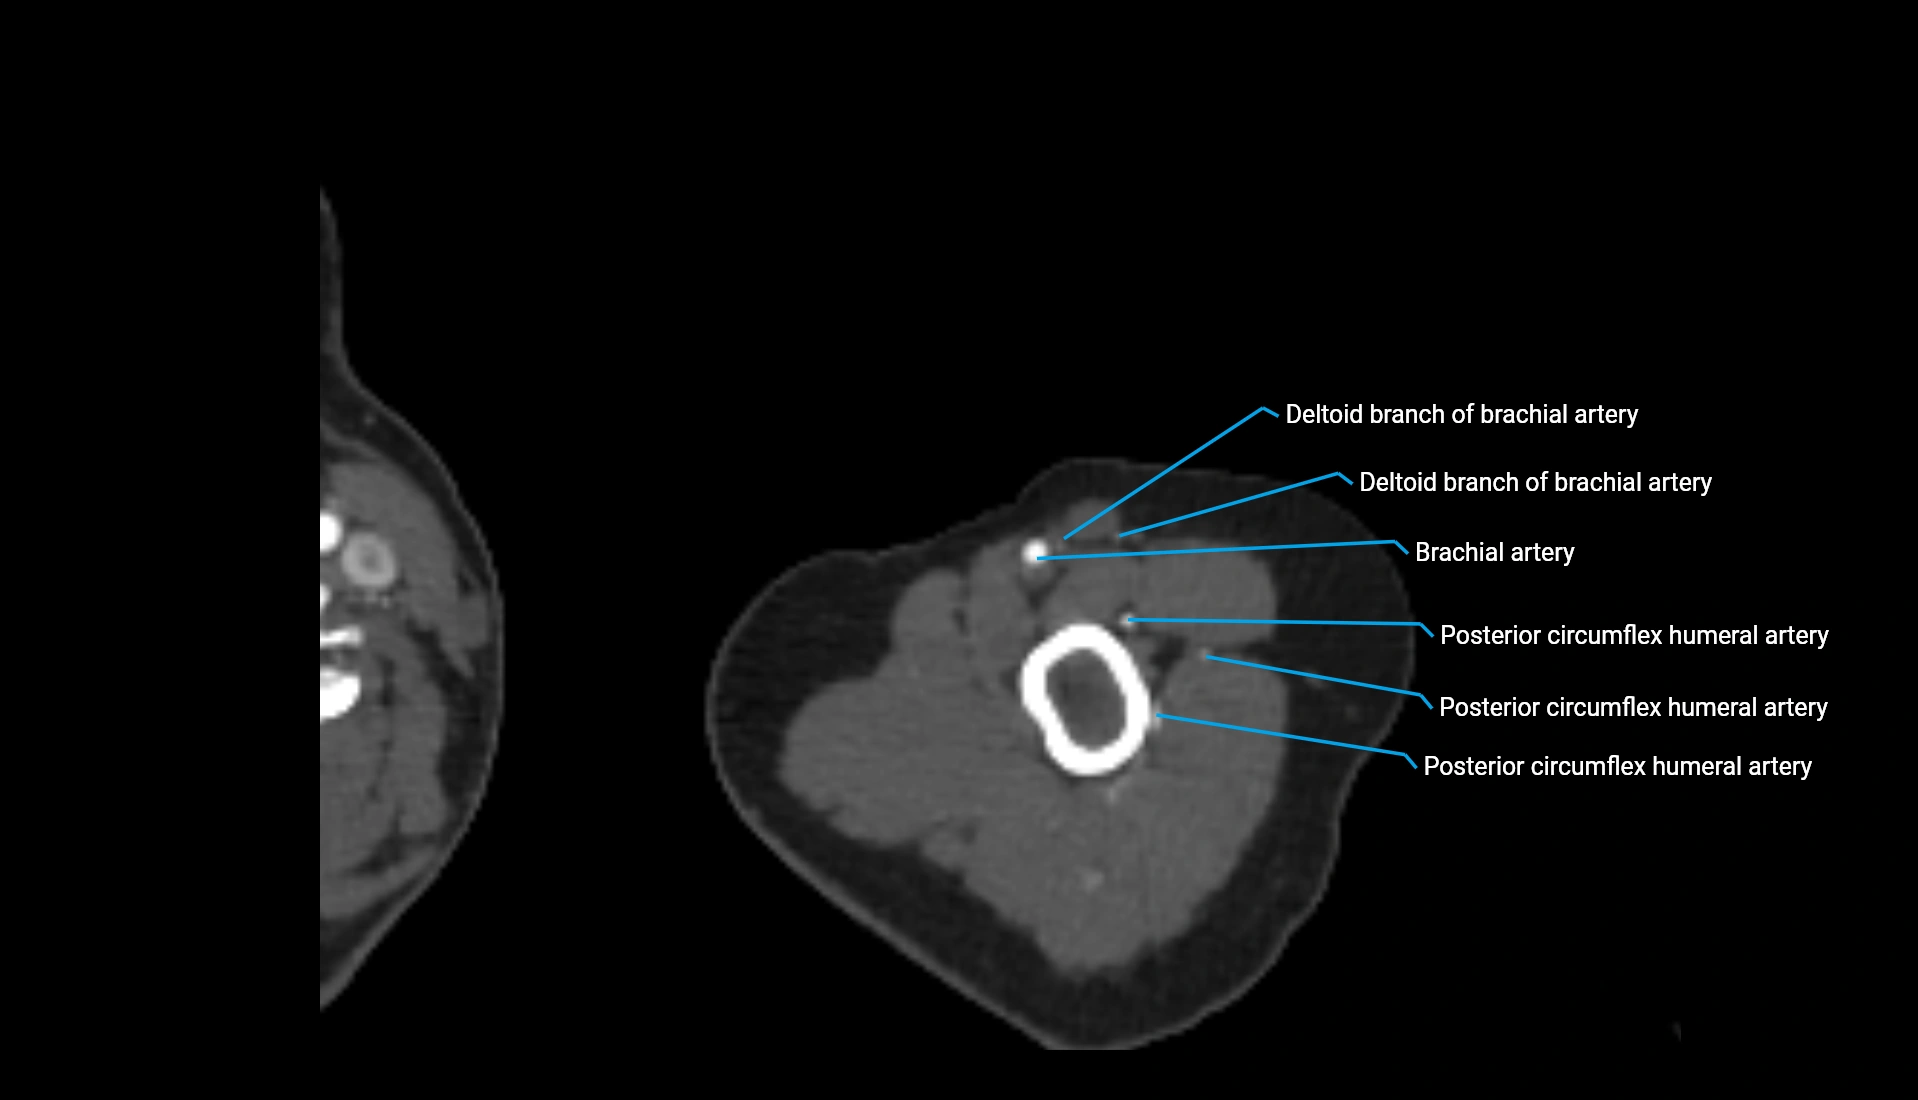

CT Appearance

Non-Contrast CT:

• Cortex: High-density, sharply defined

• Subchondral bone: Dense cancellous matrix

• Articular surface: Smooth concave contour articulating with the capitellum

• Excellent for evaluating bone integrity, alignment, and subtle fractures